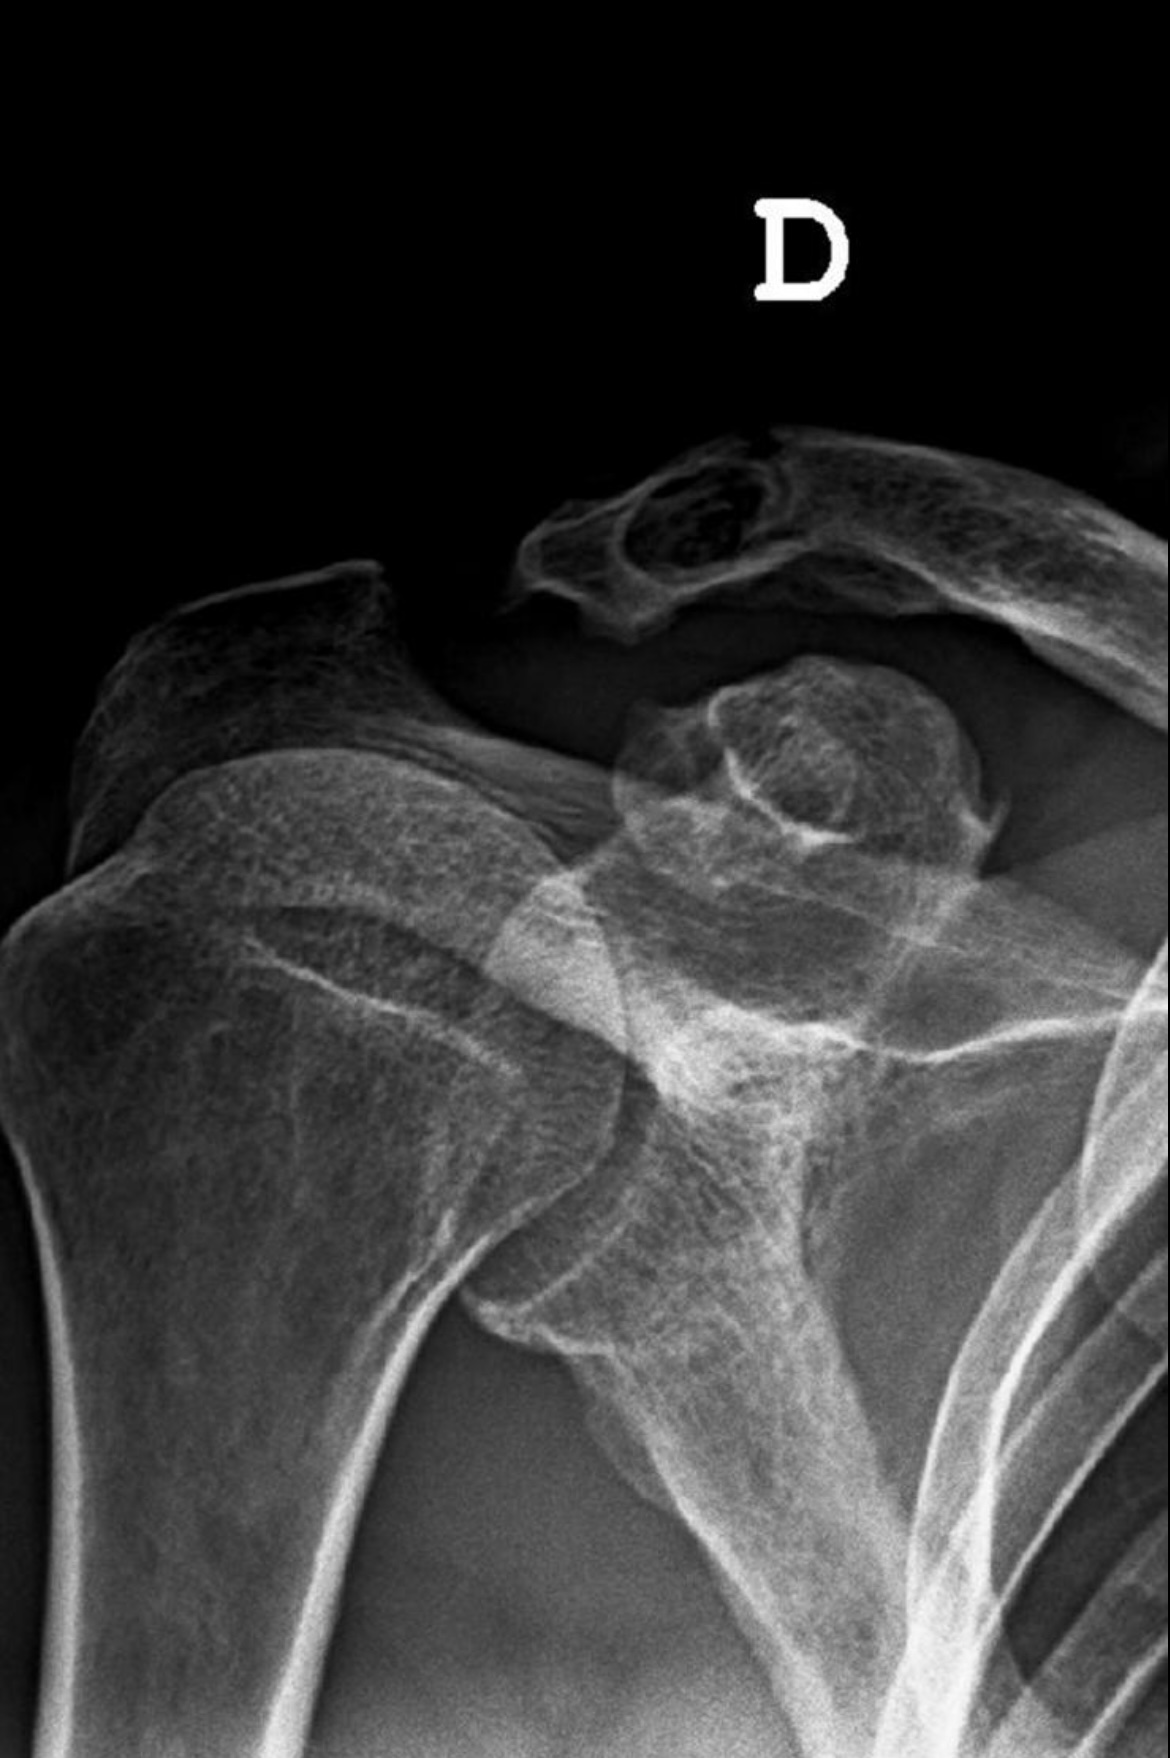

Hombre de 65 años fumador, dislipémico y con antecedente de luxación de articulación acromioclavicular hace 30 años por el que se realizó intervención quirúrgica. Presenta dolor y limitación de la movilidad en el hombro derecho tras caída de bajo impacto. Sin fiebre, pérdida de peso ni otros síntomas sistémicos.

Presenta fractura distal de clavícula no desplazada de bajo impacto sobre lesión osteolítica. Por lo que el diagnóstico diferencial de lesión osteolítica incluye: lesión secundaria a material quirúrgico implantado durante una cirugía de luxación acromioclavicular previa, artrosis por mala alineación residual o estrés mecánico crónico en la articulación, hiperparatiroidismo, gota tofacea, hipofosfatemia, proceso neoplásico, osteomielitis, tuberculosis, histiocitosis de célula de Langerhans, quiste óseo aneurismático y mieloma múltiple.

Realizar una evaluación radiográfica para distinguir la osteólisis de otras patologías. Solicitar una analítica para identificar déficits de vitaminas y minerales (como calcio y vitamina D) y descartar alteraciones endocrinas. Revisar estudios previos del paciente. El tratamiento incluye inmovilización, analgesia, rehabilitación y si es necesario cirugía.

Las intervenciones quirúrgicas que utilizan bandas o dispositivos de fijación suspensoria ajustables pueden causar la erosión ósea de la clavícula, debido al roce continuo o presión del dispositivo, y las posteriores fracturas distales de la clavícula tardías. La fisioterapia y la inmovilización correcta son cruciales en el manejo de las fracturas especialmente para prevenir complicaciones como la capsulitis adhesiva. Como medidas presentivas en fractura ósea de bajo impacto incluye la evaluación de la vitamina D, monitorización de la función renal y densiometría ósea. Además, se destaca la importancia del abordaje integral y el enfoque multidisciplinario.